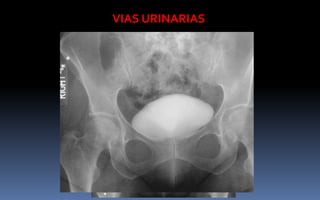

VIAS URINARIAS